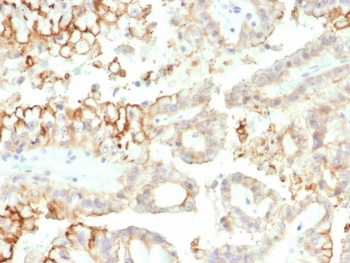

IHC staining of FFPE human kidney carcinoma tissue with B7-H3 antibody (clone B7H3/4313) at 2ug/ml. HIER: boil tissue sections in pH 9 10mM Tris with 1mM EDTA for 20 min and allow to cool before testing.

Applications Immunohistochemistry (FFPE) : 1-2ug/ml for 30 minutes at RT